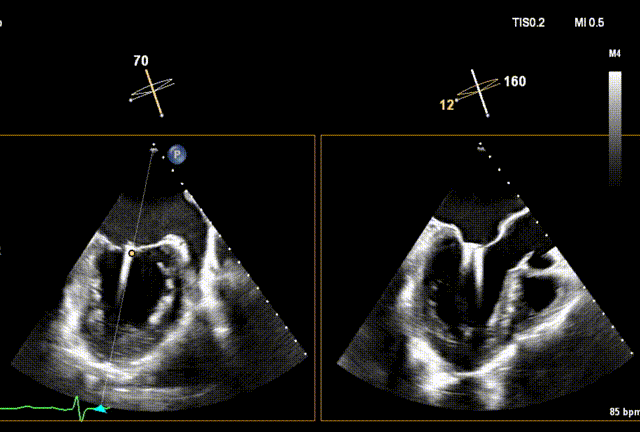

术前经食道超声(TEE)评估

术前3D

术前TEE

DMR P2脱垂连枷(脱垂范围:12mm,连枷间距:3mm),反流2区,MR重度(VC:4* 10mm),A2:21mm,P2:10mm,AP:30mm,MVA约 4.7 cm²。